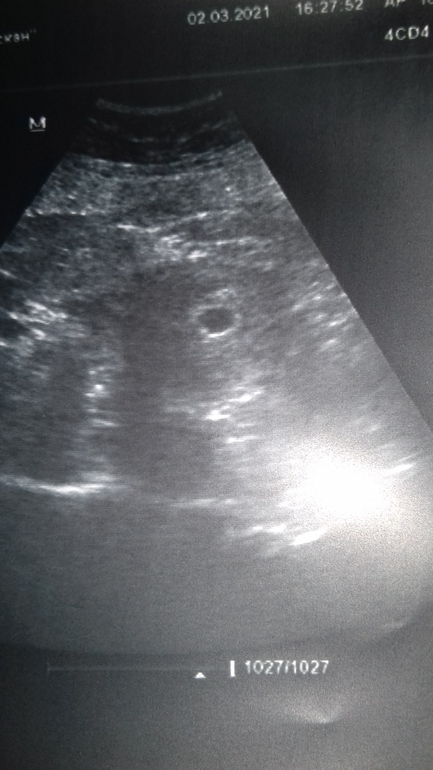

Беременность- 1 триместр ( только до 10 недель)Итак девчонки, сходила я на УЗИ ☺️ Нас нашли... врач сразу как увидела сказала, что видит и эмбриончик и его сердцебиение.. я конечно ниче не понимала, но кружок увидела а матке и в нем малюсенький комочек😁Блин как она мне сказала, что видно сердцебиение, у меня слеза скользнула.. слава богу в маске лежала... Но меня смутило, что она мне срок не 6+3 поставила, а 5 недель где то...🤔хм... последние М были 17.01.... О была 30.01-31.01...... нууу 6+3 же у меня 😒 мы что остаем на неделю???